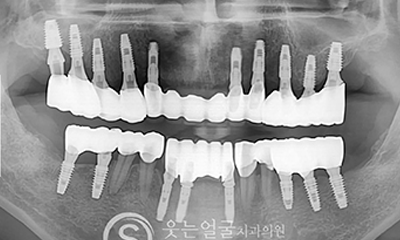

8천여건의 다양한

임플란트 수술 케이스

다년간 축적된 8,000여 건 이상의

임플란트 수술 경험을 바탕으로,

환자 개개인의 구강 구조와

상태에 최적화된 안전하고 정확한 시술을 제공합니다.